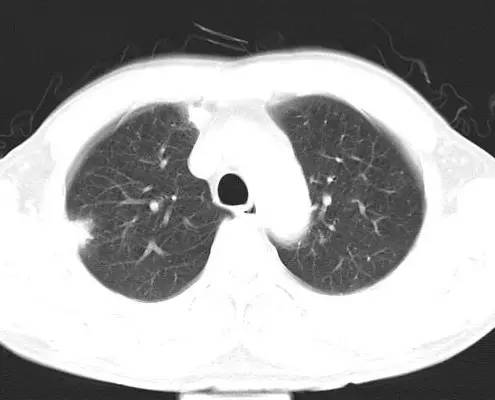

治疗前CT(图1-8):两肺胸膜下散在多发斑片状、结节状伴空洞影,边缘欠清晰。